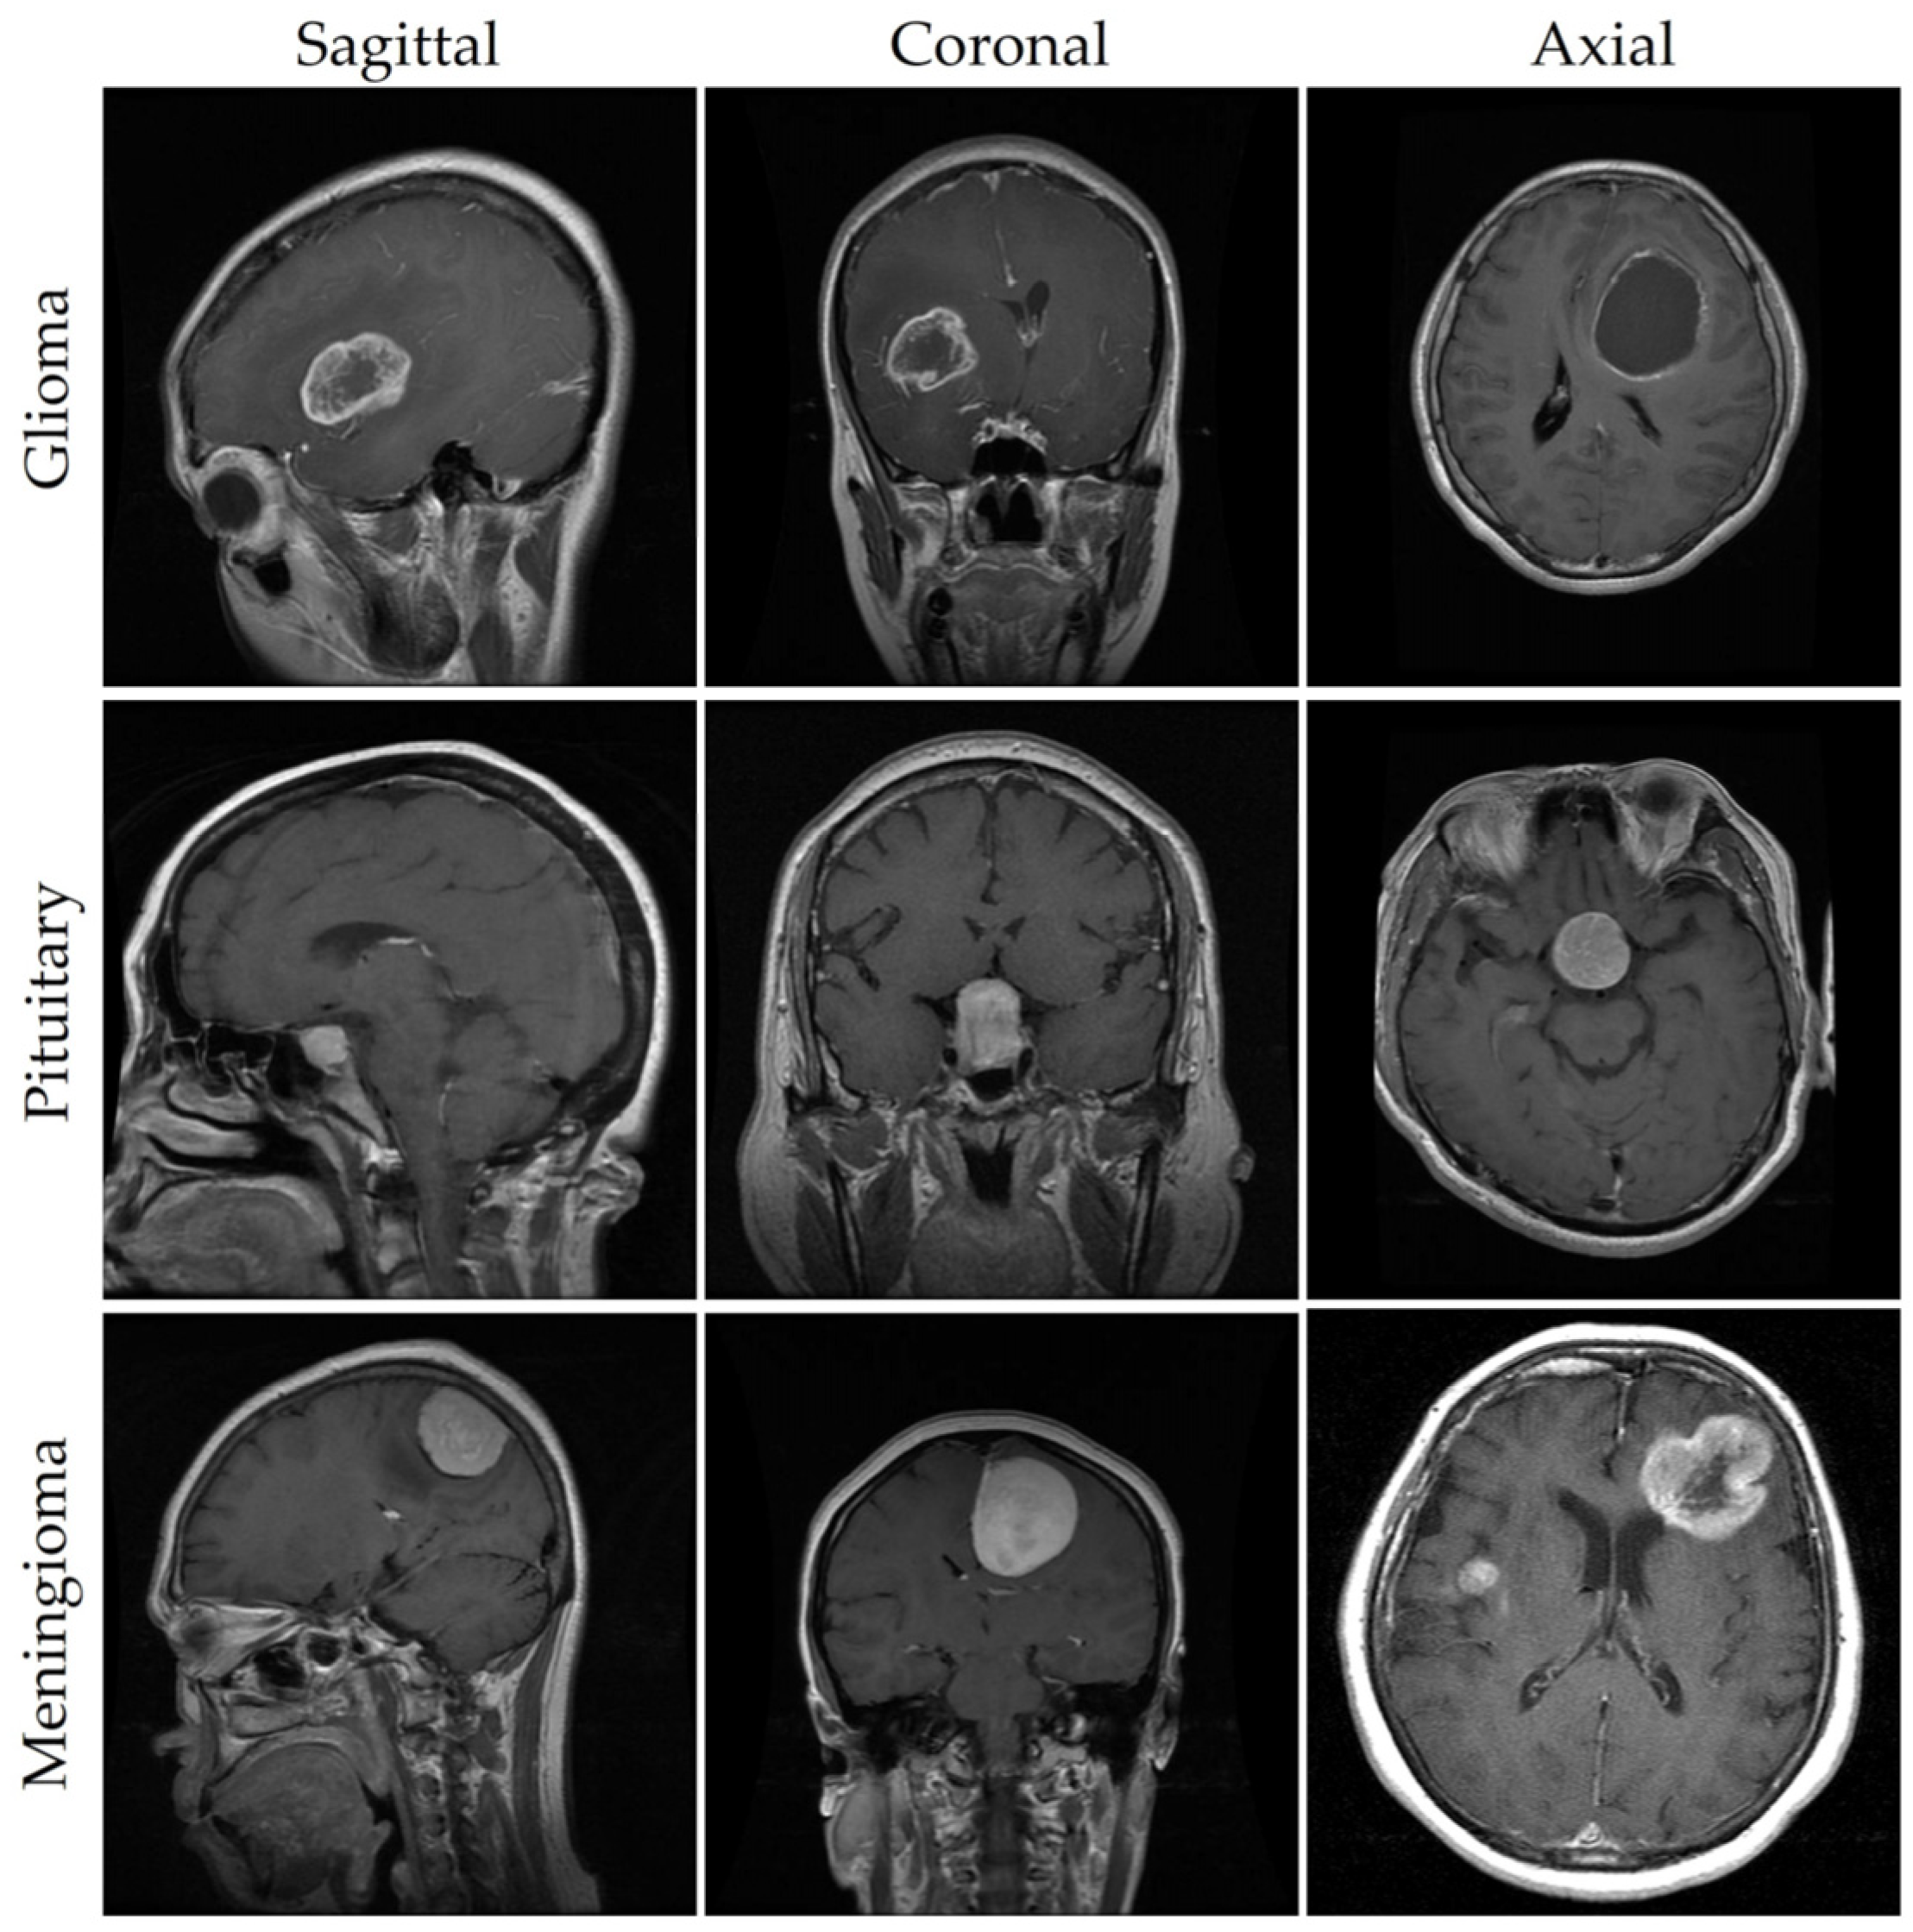

| Class | Coronal | Axial | Sagittal | Total |

|---|---|---|---|---|

| Meningioma | 232 | 208 | 268 | 708 |

| Glioma | 493 | 494 | 439 | 1426 |

| Pituitary | 321 | 291 | 318 | 930 |

| Total | 1046 | 993 | 1025 | 3064 |